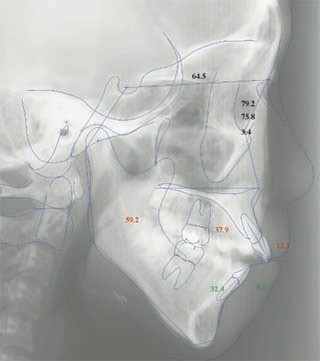

主訴:顎が歪んでいる 下顎が出ている

診断名:骨格性下顎左方偏位を伴う骨格性下顎前突

年齢:28歳

使用した主な装置名:TPB、マルチブラケット装置

抜歯/非抜歯および抜歯部位:抜歯(上顎左右第一小臼歯)

治療期間:動的処置2年3か月、経過観察3年

費用の目安:保険適応 自己負担金として30~50万

リスク、副作用:外科手術によるリスク、マルチブラケット治療に伴う歯根吸収など偶発症が発生するリスクがある。

強い下顎前突と下顎の左方変位がみられます。成長を終了した永久歯列ですので、骨の大きさのズレへのアプローチは大きく別れる所です。程度が小さければ、歯の傾きで補うように解決しますし、大きなズレであれば、外科的に骨のズレを改善する治療が選択されます。前後のズレ、左右のズレと条件が重なってきた場合、より外科矯正での改善が望ましいものとなるでしょう。

一般的な外科矯正治療の流れは、術前矯正・外科矯正・術後矯正・保定治療と移行します。術前矯正では、手術を行う時点で、上下がぴったり合うような歯列に仕上げる事になりますので、逆に言えば、手術をしていない直前においては、とんでもなく噛めない状態となっている事が多いです。このケースでは下顎のみのセットバック(後退術)をSSROにて行いました。